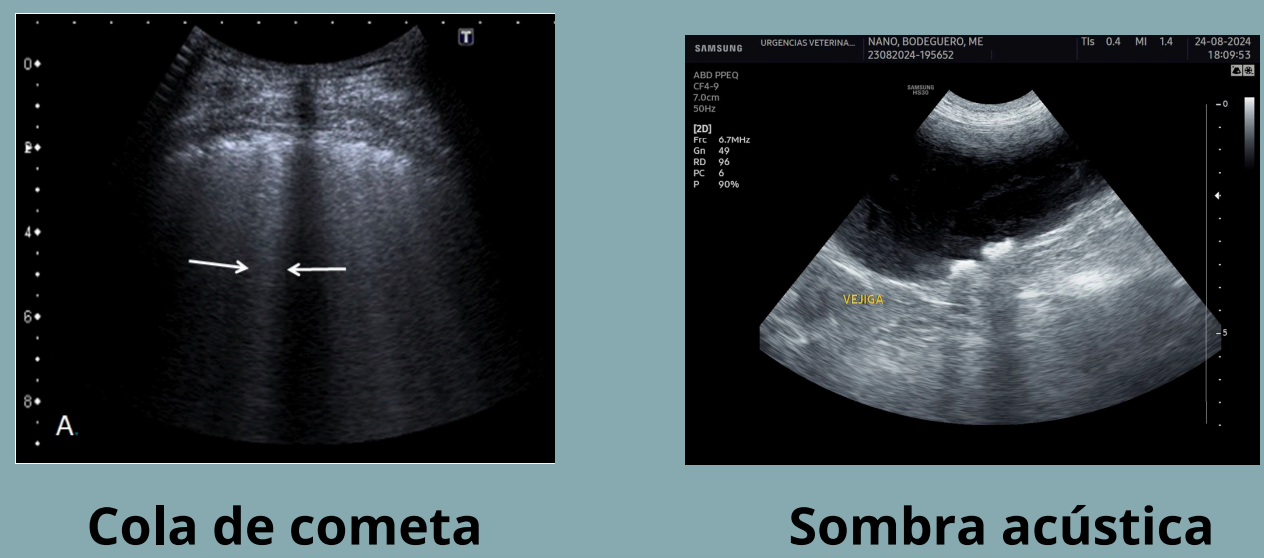

Artefactos: Cola de cometa:

- Como el de reverberación, tambien se quedan atrapadas las ondas en gas pero en vez de ser una masa son pequeñas burbujas. Se ve como multiples refracciones proximas entre si

- El resultado son lineas hiperecogenica corta y brillante que se estrecha en profundidad

- Ejemplo: aire en pulmon, pequeños cuerpos metalicos

NO CONFUNDIR COLA DE COMETA Y SOMBRA ACUSTICA. La cola de cometa presenta haces hiperecoicos, la sombra acustica haces hipoecoicos.

Sombra acústica

- Las ondas de sonido no pueden atravesar una estructura densa (material mineral) o un estrato de gas.

- La imagen generada presenta una línea superficial hiperecogénica que describe la superficie de la estructura, a partir de la cual, pierdo completamente la visualización de los estratos profundos (región oscura).

- Sombra acústica: zona negra detrás de estructuras muy densas como hueso o cálculos.

- Cola de cometa: línea brillante corta y afilada causada por burbujas de gas o cuerpos metálicos pequeños.